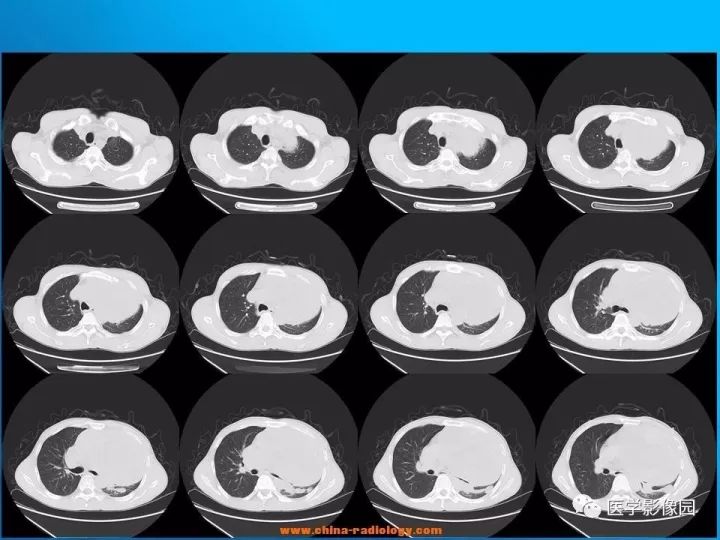

【病例】纵隔恶性神经鞘瘤1例CT

诊断结果:恶性神经鞘瘤

CT表现

1.肿瘤多为单发,平扫密度略低于肌肉,轮廓光整,呈类圆形或卵圆形,肿瘤较大时可为不规则形或呈分叶状,易囊变,常为囊实性,有包膜,可有钙化。

3.当肿块体积较大,并向周围侵犯,其内密度混杂,尤其是囊变、坏死明显;实性部分呈斑片状及网格状较明显强化;往往提示为恶性神经鞘瘤。